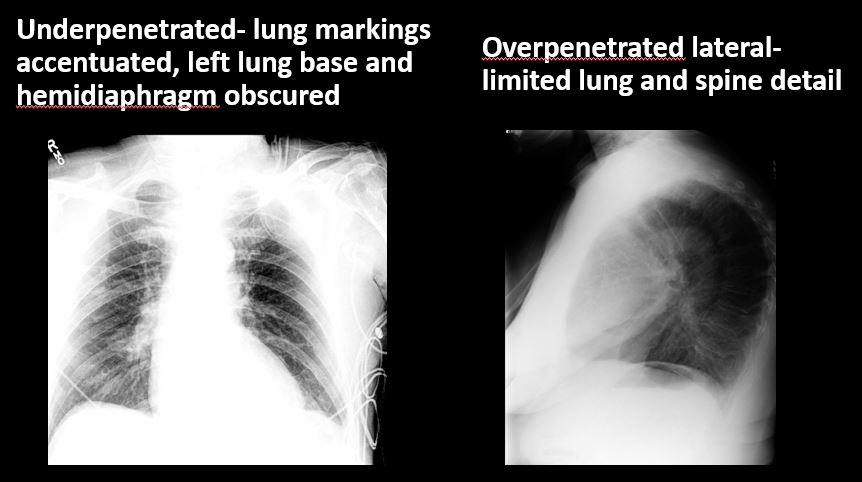

Technique

The exam is expiratory, rotated, over or under penetrated, or limited by overlying structures or soft tissues, body habitus, patient positioning, or motion. [Yes/No]